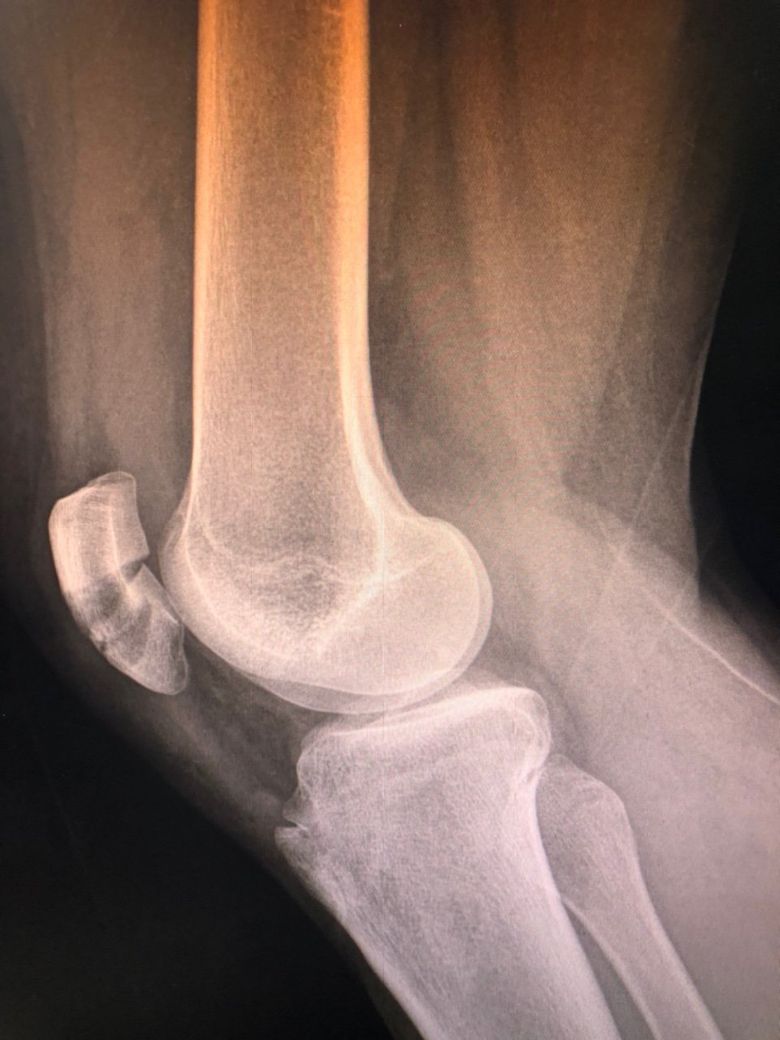

가게에서 나오다 동그라미친 턱에 왼쪽 발목이 접질리면서 그대로 고꾸라져서 오른쪽 무릎으로 넘어졌어요

무릎슬개골 박살 인대까지 다 찢어져서 철심박고 깁스 5주에 재활치료 예정입니다 이경우에도 시청에서 보상 받을 수 있을까요?